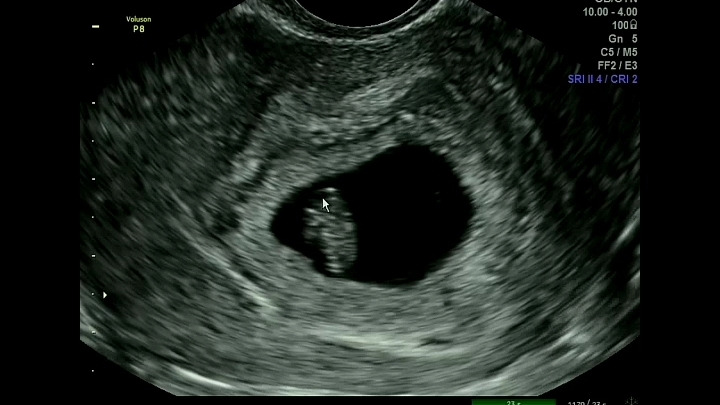

흐릿한 1.4cm의 덕순이

아직 사람 모습도 아닌 덕순이에게 엄청난 모성애를 느끼는 것은 아니다.

내가 본 덕순이 모습은 초음파 사진으로 본 희끄무레한 물체였다.